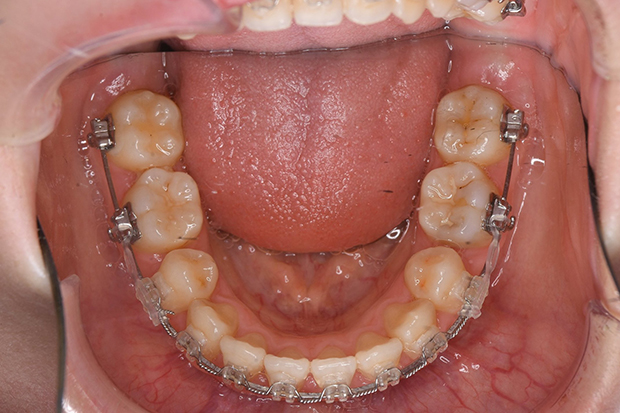

【埋伏歯】下顎前突 小児矯正 表側マルチブラケット装置

| 主訴 |

上の歯が出てこない 受け口 |

||

|---|---|---|---|

| 診断名 |

上顎左側中切歯、側切歯の埋伏歯および側切歯、犬歯の移転歯を伴う反対咬合 |

||

| 年齢 | 8歳 | 性別 | 女子 |

| 治療に用 いた装置 |

舌側弧線装置 唇側マルチブラケット装置 (メタルワイヤー) | 抜歯部位 | 非抜歯 |

| 治療期間 ・回数 |

3年10か月・46回 | 治療費 概算 |

約40万円 (調整料を含む) |

| 治療内容 詳細 |

前歯が生えてこないのをかかりつけの歯科医院にて指摘され、ご紹介された患者様です。虫歯も多い子でしたが、虫歯の治療、管理も同時に行い、小児矯正だけで綺麗に治りました。 |

||

| リスク・ 副作用 |

装置による違和感 疼痛 虫歯のリスクなど |

||